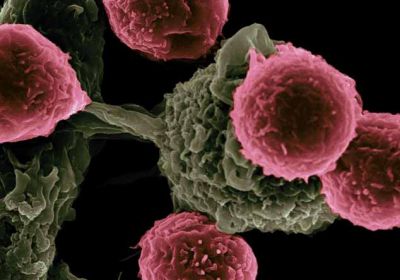

कैंसर के उपचार में सहायक पौधे की कोशिकाएं की गई विकसित

29 Dec, 2023 04:34 PM IST | ASIAVARTANEWS.COMआईआईटी मद्रास और आईआईटी मंडी ने एक खास पौधे की कोशिकाओं को मेटाबॉलिक रूप से...